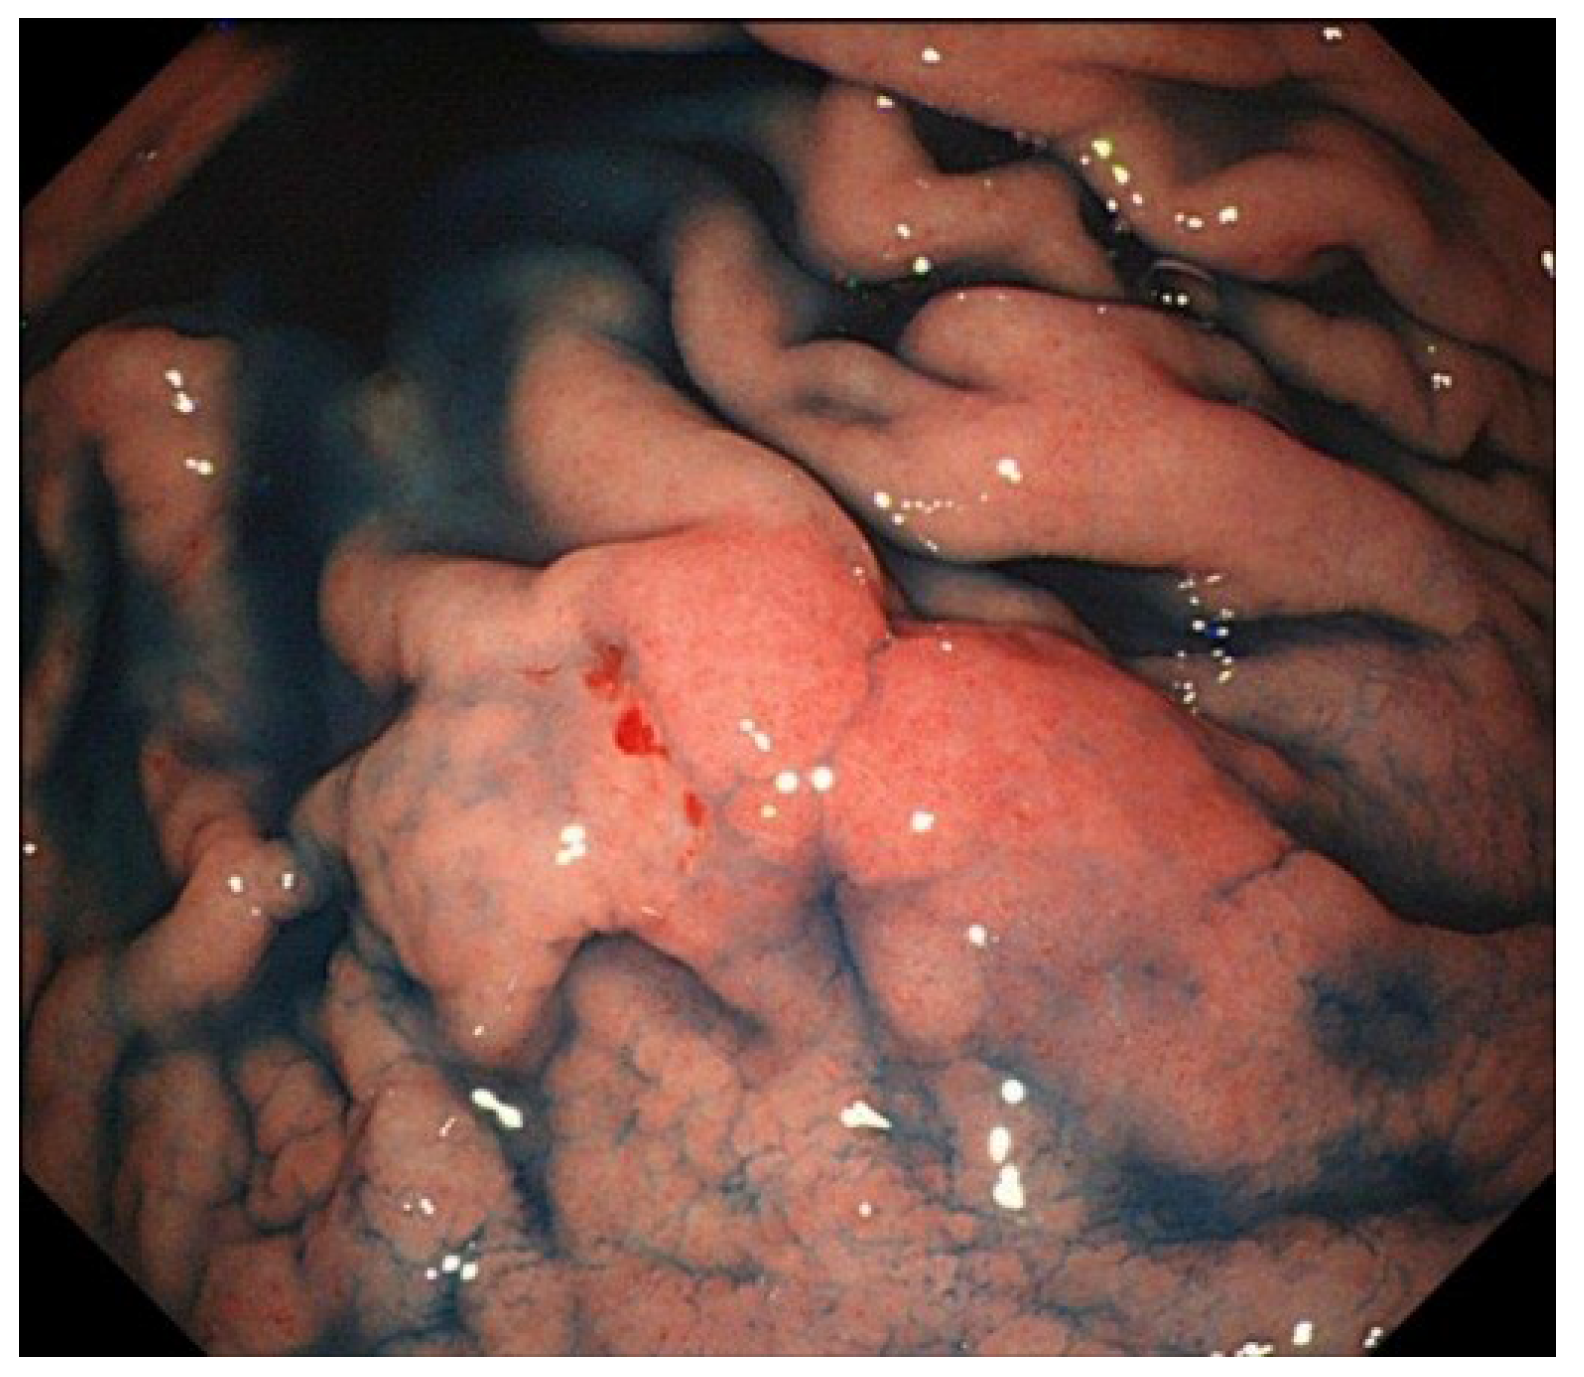

- Yanai, H.; Nishikawa, J.; Mizugaki, Y.; Shimizu, N.; Takada, K.; Matsusaki, K.; Toda, T.; Matsumoto, Y.; Tada, M.; Okita, K. Endoscopic and pathologic features of Epstein-Barr virus-associated gastric carcinoma. Gastrointest. Endosc. 1997, 45, 236–242. [Google Scholar]

- Nishikawa, J.; Yanai, H.; Mizugaki, Y.; Takada, K.; Tada, M.; Okita, K. Case report: Hypoechoic submucosal nodules: A sign of Epstein-Barr virus-associated early gastric cancer. J. Gastroenterol. Hepatol. 1998, 13, 585–590. [Google Scholar]